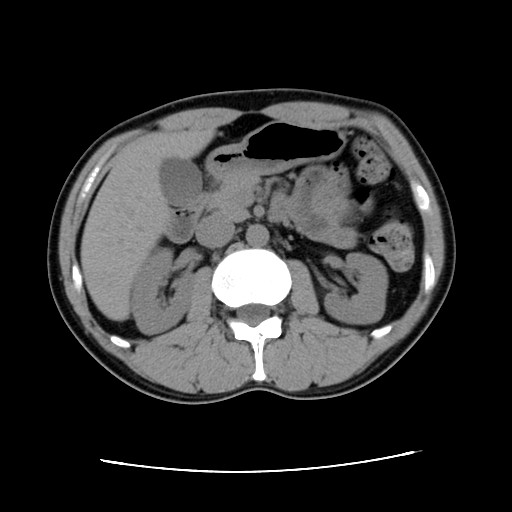

【CT画像】

単純CT:特に変化を認めず。 【腫瘍マーカー】 HCGβ:<0.1 問題なしでした! 今日は画像はありません。 理由は、病院側でデジタル化が進んでいて、PCモニターでの画像確認となったからです。 今日はフィルムも用意されませんでした・・・・。 先生曰く、そのうちフィルムもなくなるだろうと。 そのときにはCD-R等に焼く対応もするようになっているはずだと。 早くデータで画像がほしい。その時はたくさんアップしますw。 次回は2月です。

今回からCTの造影剤はありませんでした。

勘違いしてた・・・ なので単純CT。 横になって撮るだけなので非常に楽ですね。その分撮影される画像も解像度が低くなりますが・・・ しかし、思えば2005年末頃の単純CTからリンパ転移が疑われ始め、その次からはずっと造影剤を使用したCTだったわけだ。 2008年末の今、やっとそこへ戻ってきたという感じがした。 検査後の帰り、病院の最寄り駅のパン屋で朝食。 改札横に店があるのでガラス越しに行き交う多くの人を眺めながら思う。 2006年の入院中、ヨメも色々思いながらここを通ったんだろう、と。 何ヶ月も。 暑い日も雨の日も。 ただただ「感謝」あるのみです。 本日の検査結果は12/8。